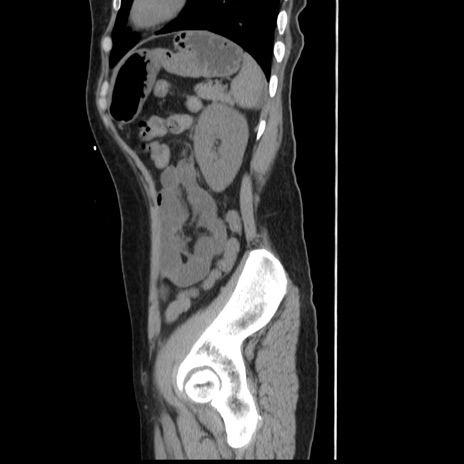

症例10(矢状断像)

【症例】 50歳代女性

【主訴】 腹痛

【現病歴】前日生レバーを食べた。今朝に排便あり。 昼前に突然発症の腹痛を生じ、当院救急外来を受診した。

【既往歴】 子宮筋腫にてで子宮全摘後

【身体所見】 意識清明、腹部:平坦、軟、下腹部やや左を中心に圧痛・反跳痛あり、筋性防御あり

【データ】WBC 7800、CRP 0.07